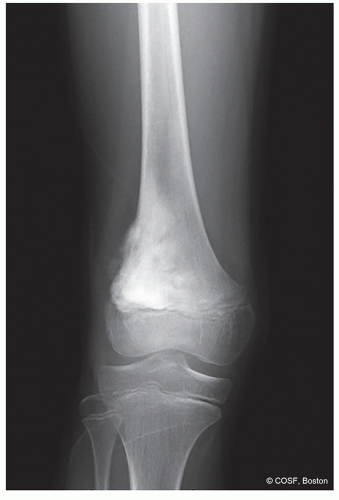

How is the bone responding to the tumor: margination, periosteal reaction? (Figures 41.1,41.2,41.3,41.4,41.5,41.6,41.7,41.8,41.9)

Malignant: osteosarcoma chondrosarcoma, undifferentiated pleomorphic sarcoma of bone (see Figure 41.3)

Diaphysis: Ewing sarcoma (see Figure 41.4)